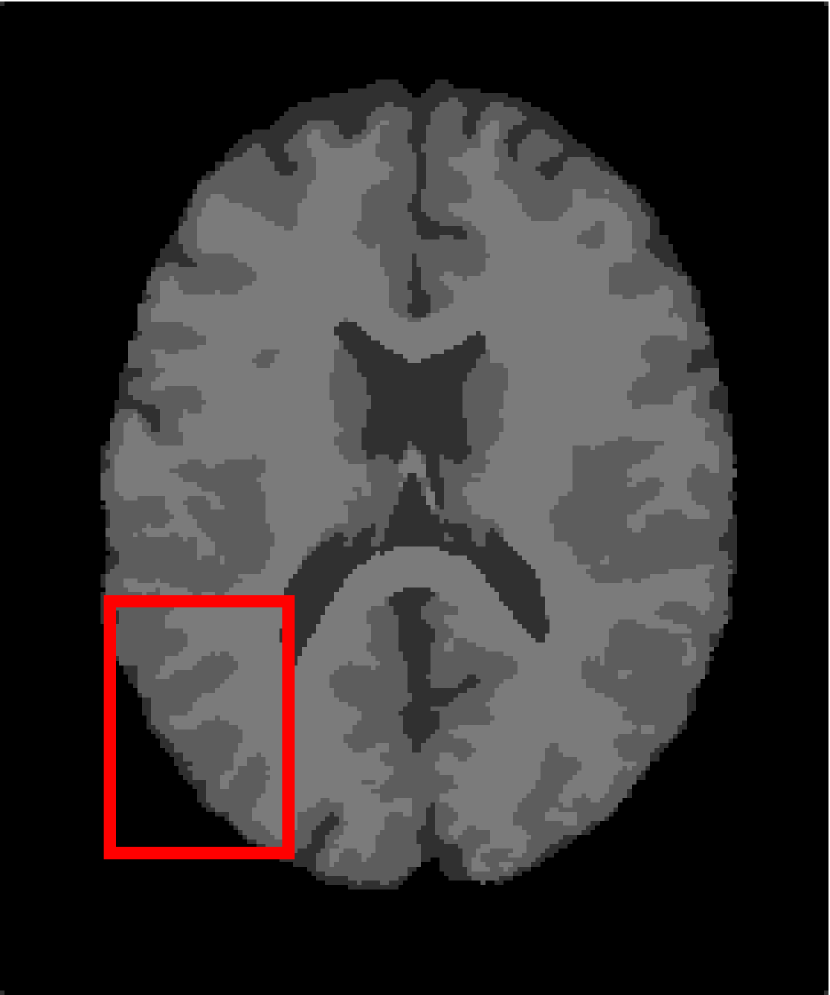

Next, we representatively segment five medical images from BrianWeb. They are represented as five slices in the axial plane with a sequence of 70, 80, 90, 100 and 110, which are generated by T1 modality with slice thickness of 1mm resolution, 9% noise and 20% intensity non-uniformity. Here, we set c=4𝑐4c=4 for all cases. The comparison between WRFCM and its peers are shown in Fig. 9 and Table II. The best values are in bold.

Figure 9: Segmentation results on five medical images. The parameter: ϕ=5.35italic-ϕ5.35\phi=5.35. From top to bottom: noisy images, ground truth, and results of FCM_S1, FCM_S2, FLICM, KWFLICM, FRFCM, WFCM, DSFCM_N, and WRFCM.

By a view of the marked red square in Fig. 9, we find that FCM_S1, FCM_S2, FLICM, KWFLICM and DSFCM_N are vulnerable to noise and intensity non-uniformity. They give rise to the change of topological shapes to some extent. Unlike them, FRFCM and WFCM achieve sufficient noise removal. However, they produce overly smooth contours. Compared with its seven peers, WRFCM can not only suppress noise adequately but also acquire accurate contours. Moreover, it yields the visual result closer to ground truth than its peers. As Table II shows, WRFCM obtains optimal SA, SDS and MCC results for all five medical images. As a conclusion, it outperforms its peers visually and quantitatively.